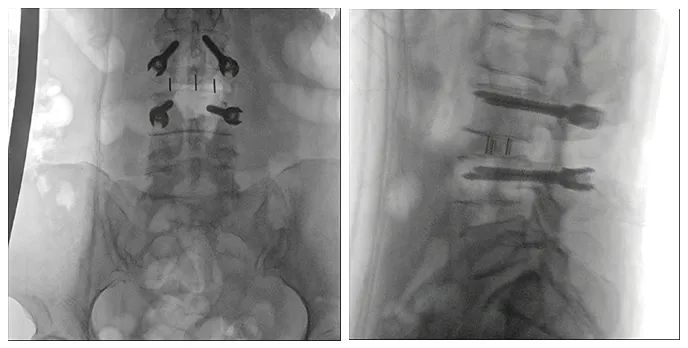

術中三維導航C臂影像

手術效果確認

使用普愛醫療術中三維導航C臂進行透視,根據透視影像引導確認責任間盤、規劃手術方案,充分暴露骨組織,并通過專業器械切除椎板,暴露神經及椎管;在C形臂的引導下,確定責任間盤上下椎體椎弓根位置,制定進針點及進針方向,沿椎弓根方向植入脊柱螺釘進行固定;放入椎間融合器,加固螺釘。最后再進行C形臂透視,確認手術的完成效果。